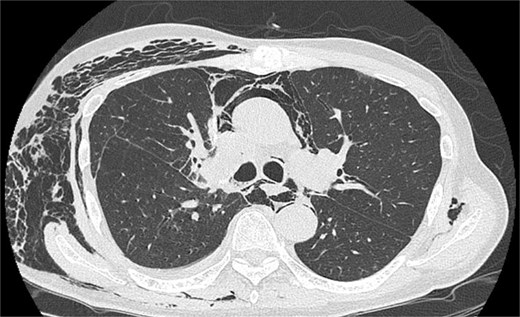

On POD 6, SE developed and spread to the chest, neck, and face. CT demonstrated remarkable mediastinal and SE with minimal lung collapse (Fig. 2; Video 2). Therefore, a chest tube was inserted, but minimal AL occurred from the chest tube, and the emphysema worsened. On POD 11, we performed thoracoscopic exploration and therapeutic intervention. Dense adhesion was confirmed between the staples on the interlobular plane and the dissected upper mediastinum. These were released, revealing the previous pleural tear. No other causative factors were observed. CT and operative findings suggested late-onset AL into the dissected mediastinum through dense adhesions. A leak test under positive pressure of up to 20 cmH2O revealed no AL from the pleural tear. The tear was sealed using a PGA sheet and fibrin glue, and 130 ml of autologous blood was injected into the pleural space to seal the dissected mediastinum and prevent air inflow (Video 3).

After the reoperation, AL was not observed, and SE regressed. The chest tube was removed on POD 5 after the reoperation (POD 16 after initial surgery). The patient was discharged on POD 18 after initial surgery. CT performed after 1 year revealed no emphysema or cancer recurrence (Fig. 3). The patient was informed of the complications and accepted the treatment outcomes.